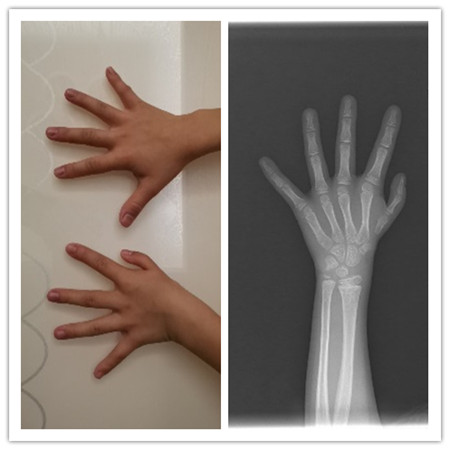

近日,玉溪市人民医院骨外三科医生在北京积水潭医院专家的指导下,成功完成玉溪首例左侧IIIB型拇指发育不良患儿的食指拇化手术治疗,患儿恢复良好出院。

拇指占据手部功能的50%,拇指的骨骼及软组织的结构特殊性,使其成为手部独一无二的不可替代的部分。拇指发育不良(thumb hypoplasia)是先天性拇指畸形中的一大类畸形。拇指发育不良表现为拇指细、小、短,功能不全,或拇指完全缺失。拇指发育不良严重影响手部抓握及对捏功能,同时畸形或缺失的拇指导致手部外观难看。

食指拇化术治疗IIIB型及以上拇指发育不良,一直被国际上奉为经典治疗方案。虽然在过去的30年里,漂浮指的治疗出现不同的方法,但食指拇化技术也在不断改进,至今为止,仍然是治疗IIIB型及以上拇指发育不良最为经典的方法,不论术后的手部外形、还是功能都优于其他手术方式。

术前

术后

玉溪市人民医院骨外三科目前可开展ponseti技术治疗儿童先天性马蹄内翻足,多指(趾)、并指(趾)、拇指发育不良、马蹄内翻足、高弓足、平足、垂直距骨等常见和罕见四肢先天畸形的手术治疗。医生提示食指拇化术最佳手术年龄为1-2岁。